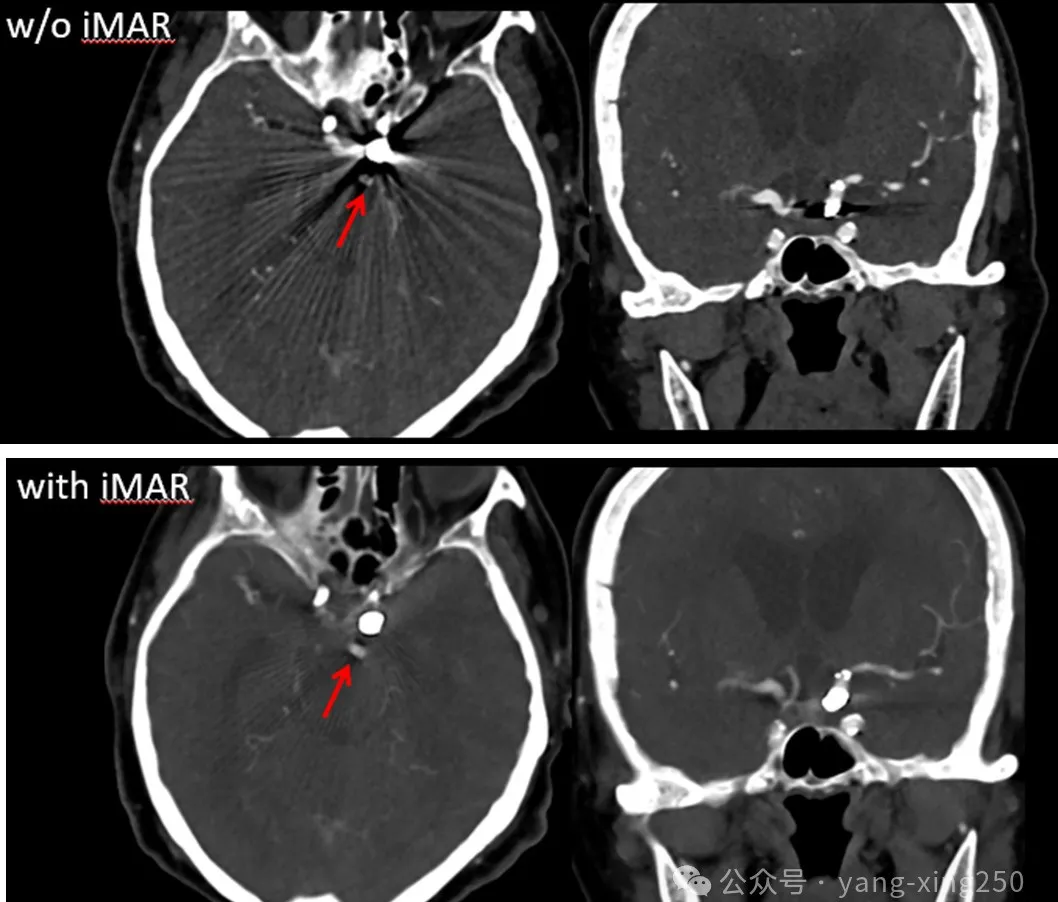

1、iMAR(iterative Metal Artifact Reduction)

原理:iMAR是通过射线束硬化矫正、线性内插值以及自适应正弦图修复和分频去金属伪影等多种迭代计算,可以明显减少图像中的条状伪影,并同时校正受影响的组织CT值,使之更接近于无金属情况下的真实值。

优缺点:在不增加辐射剂量的同时,可回顾重复使用原始数据重建,但是,对产生的严重金属伪影去除效果不理想。iMAR主要应用在光子饥饿效应引起的伪影,如人工金属髋关节置换。

注意:以上抑制金属伪影的方法并非仅能单一使用,在临床工作中,我们可以几种方法组合使用,效果如下:

也有研究表明,iMAR+双能量去金属伪影效果最佳;其次依次为双能量、iMAR。如下图: